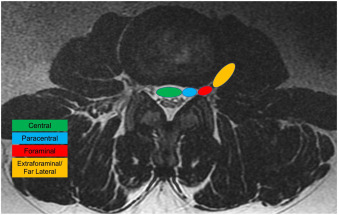

The four primary axial zones are: central, paracentral (subarticular / lateral recess), foraminal, and extraforaminal (far lateral). Each zone is defined by bony and soft tissue landmarks visible on MRI, and each has a distinct pattern of nerve root involvement. The distinction between zones is critical because, in most cases, paracentral herniations compress the traversing nerve root while foraminal and extraforaminal herniations compress the exiting nerve root at the same disc level.

On MRI, use the following anatomical landmarks to define zone boundaries: (See coronal image above)

1) The medial border of the facet joints (separates central from paracentral/subarticular zones)

2) The medial and lateral borders of the pedicles (define the foraminal zone)

3) The lateral edge of the pedicle (defines the boundary between foraminal and extraforaminal zones)

• Central

Location: Midline, within spinal canal (between medial facets)

Root Typically Affected: Cauda equina risk or bilateral traversing roots (can be unilateral depending on size and 3d geometry)

• Paracentral (Subarticular / Lateral Recess)

Location: Between lateral aspect of thecal sac and the border of the medial pedicle

Root Typically Affected: Traversing root

• Foraminal

Location: Between medial & lateral pedicle borders (within the neural foramen)

Root Typically Affected: Exiting root +/- DRG

• Extraforaminal (Far Lateral)

Location: Everything lateral to the lateral border of the pedicle

Root Typically Affected: Exiting nerve +/- DRG